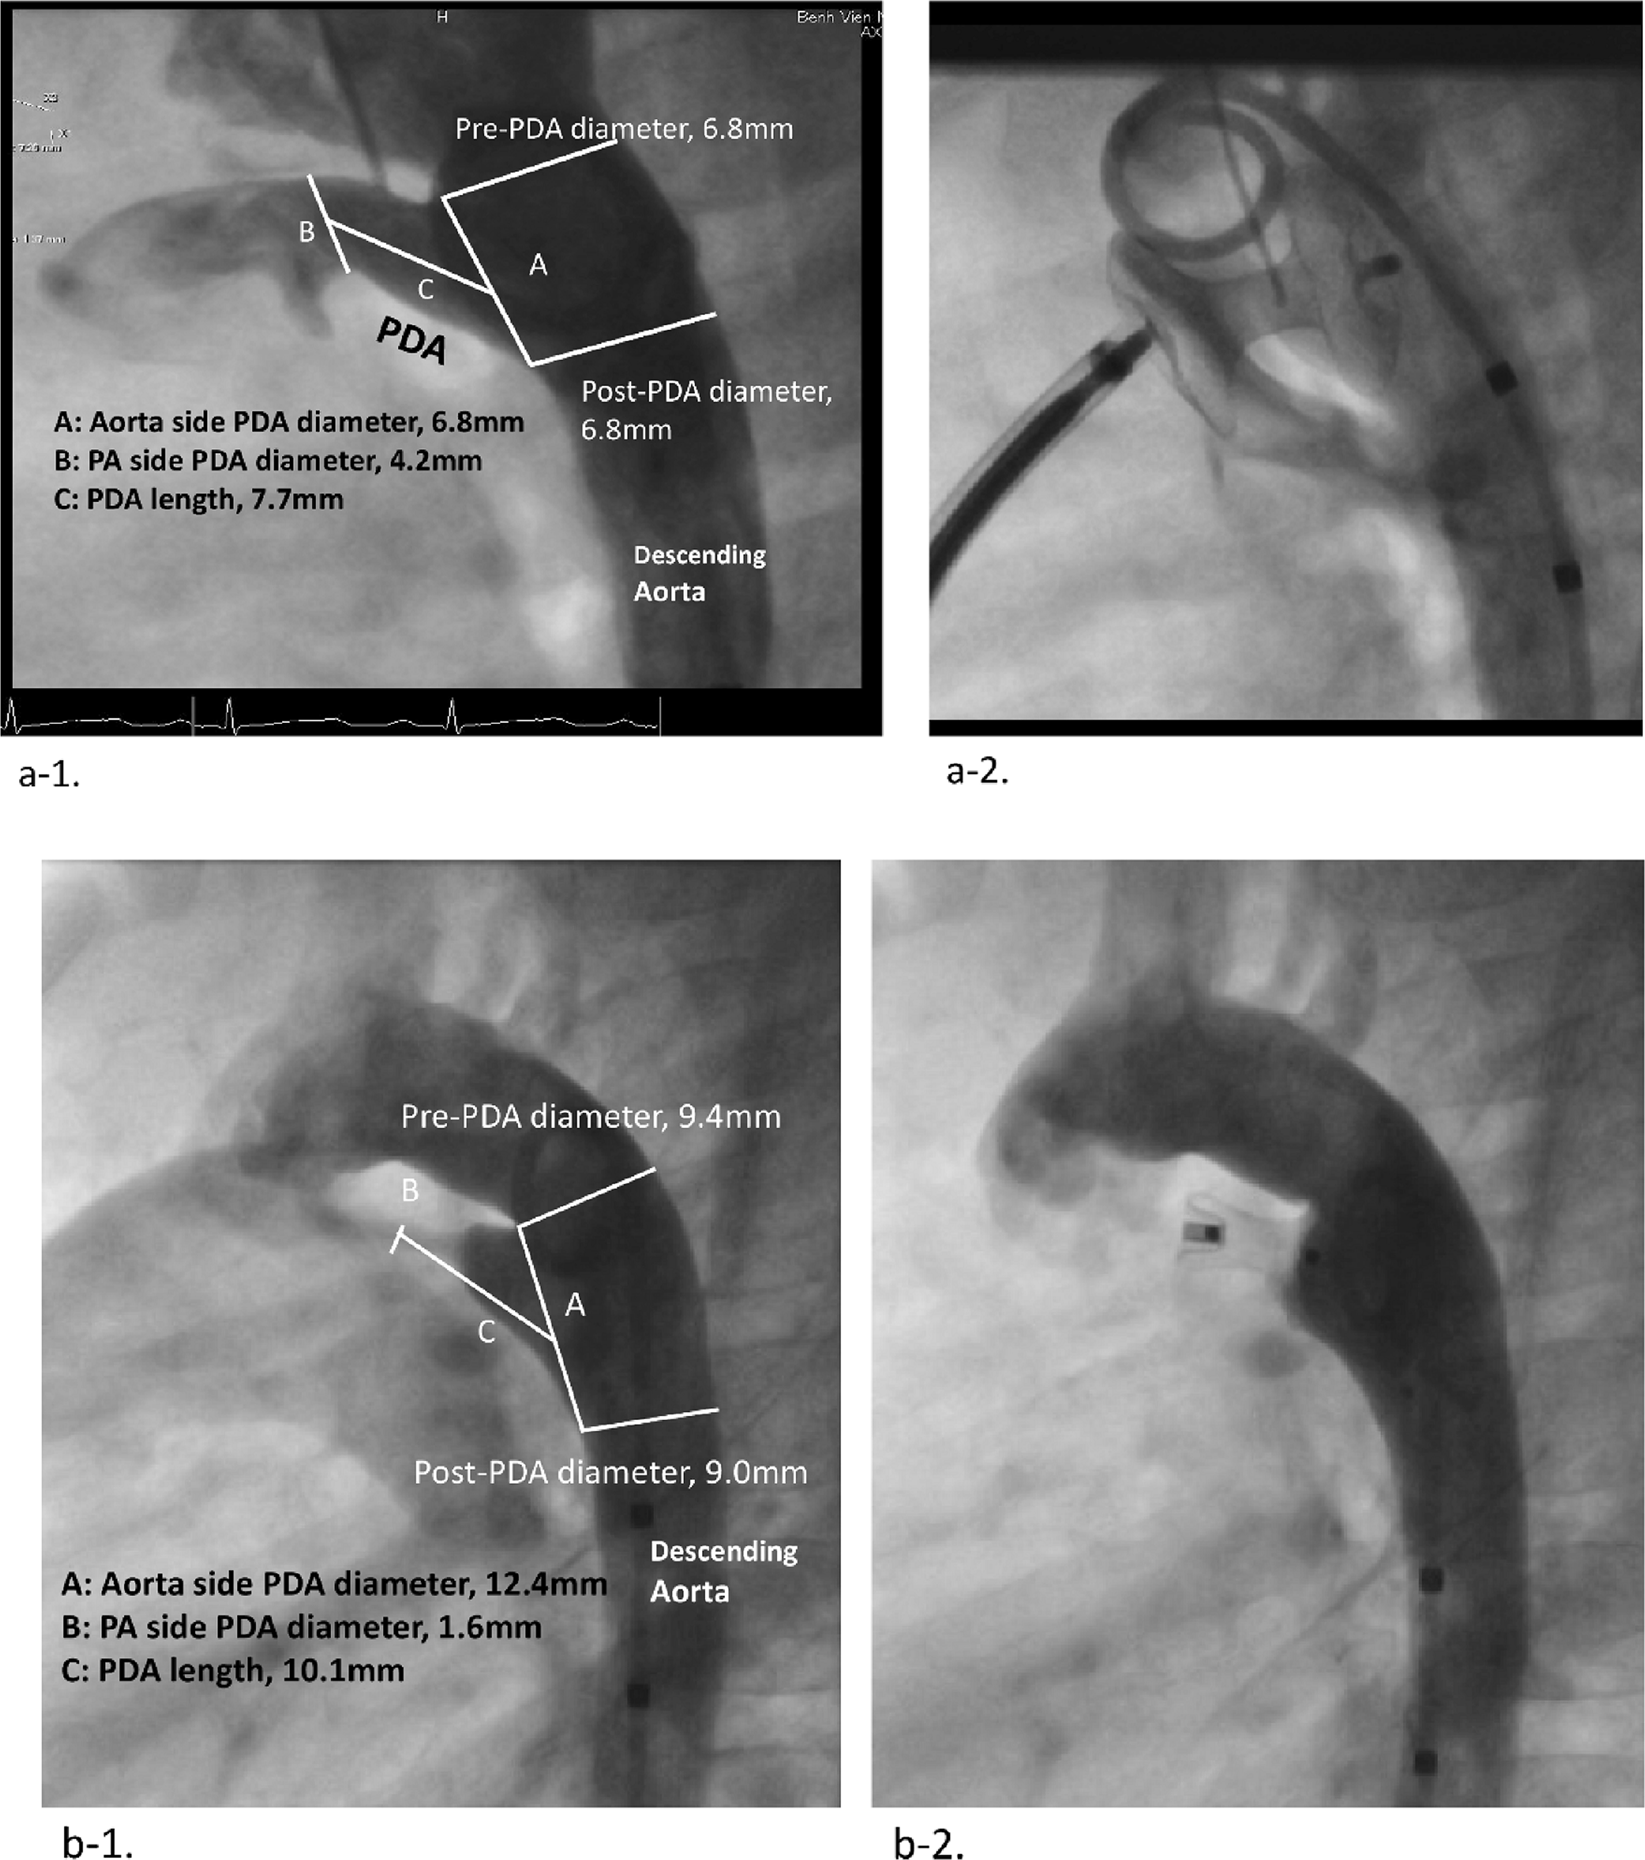

Type C PDA with CRS and type A PDA without CRS. (a) Type C PDA of a 24-month-old girl with CRS (a-1) and the closure with a muscular VSD occluder (a-2). (a) Type A PDA of 29-month-old girl (b-1) and the closure with Amplatzer™ Duct Occluder (b-1). PDA; patent ductus arteriosus, CRS; congenital rubella syndrome, VSD; ventricular septal defect.